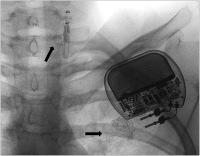

VNS-Therapie

Abbildung 2: Röntgenaufnahme bei einer 16jährigen Patientin mit sekundärem Funktionsverlust der VNS-Therapie. Makrobruch.